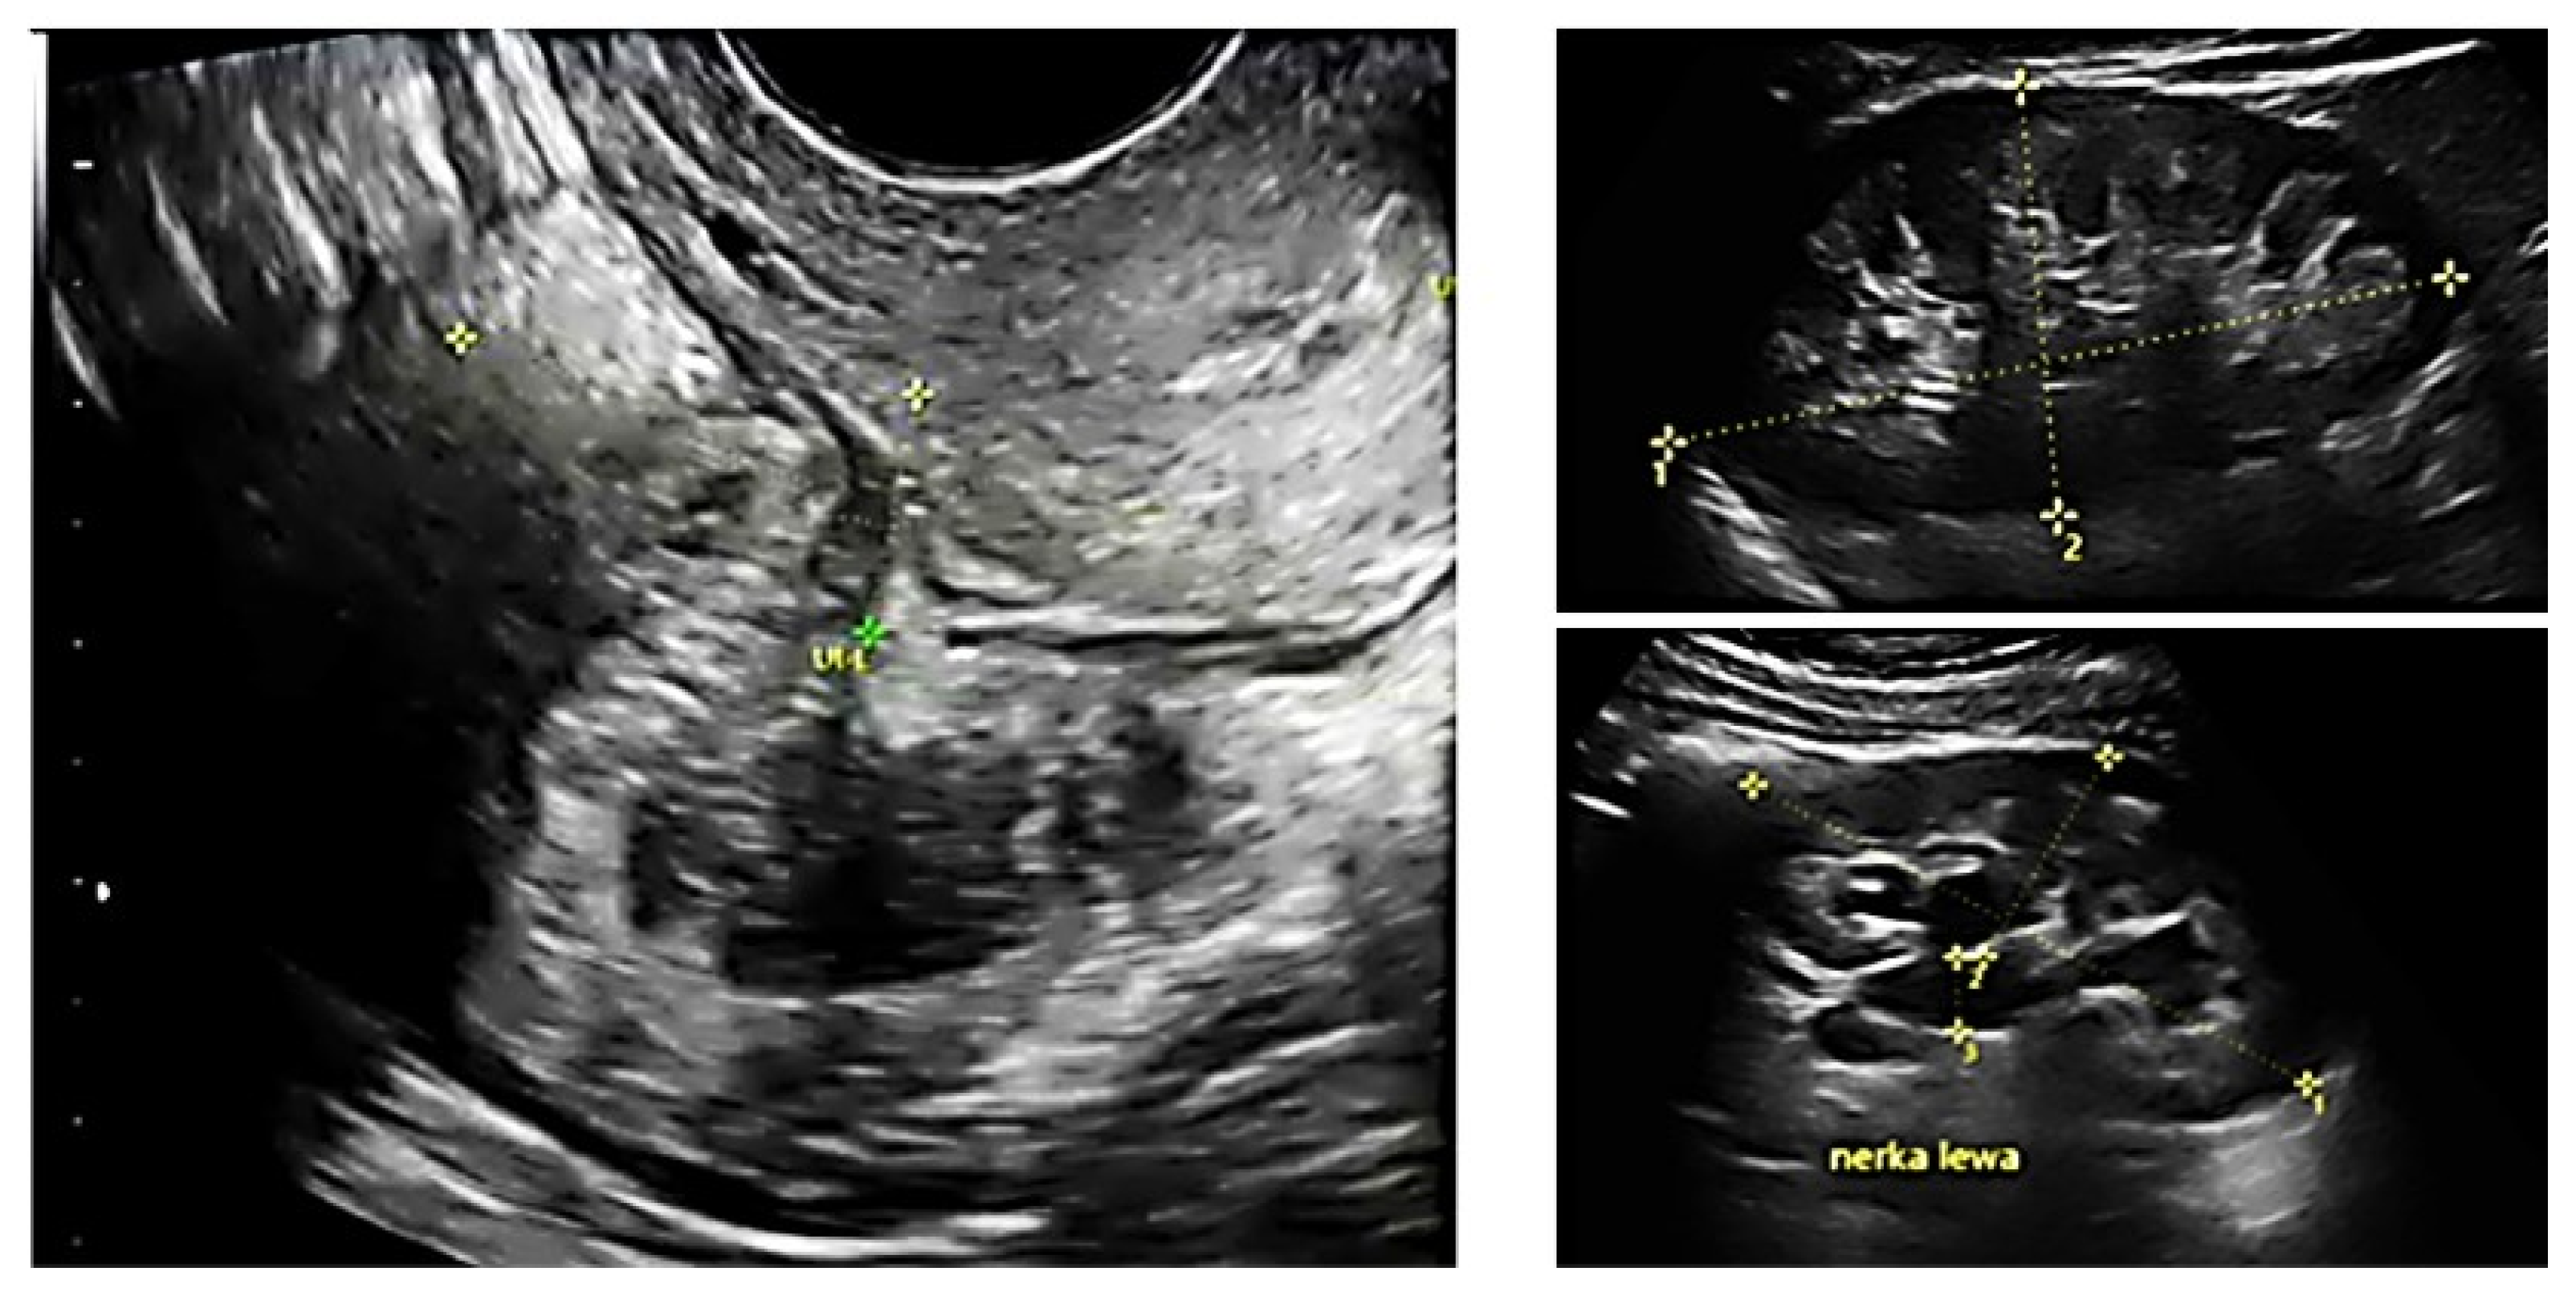

All patients underwent preoperative ultrasound examination by an expert surgeon-gynecologist—(E.M.-N.), with detailed pelvic compartments assessment via transvaginal sonography (TVS) and with kidney congestion assessment via transabdominal sonography (TAS), following an adapted protocol-based on IDEA group guidelines [6]. Examinations were performed on Voluson E8 Expert with the use of vaginal probe RIC5-9-D (depth max 16 cm) and abdominal probe RAB2-5-D, mainly for the kidney scan. A detailed report was recorded for each patient. Examples of ultrasound examination images are shown in Figure 1.

Figure 1.

Preoperative ultrasound examination: the bowel DE nodule (TVS exam), congestion in the left kidney (TAS exam).